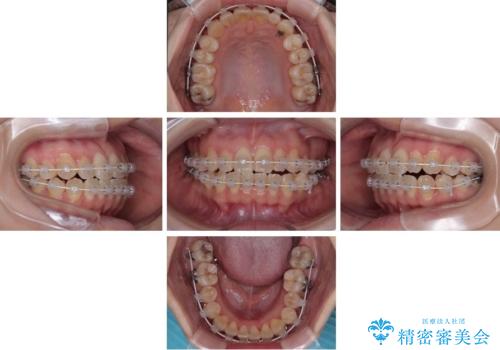

- 20代女性

- 矯正装置

- 審美装置

- 患者様は「歯並び全体のデコボコが気になり、人前で笑うことに抵抗がある」とのことでご来院されました。

診査の結果、上下顎ともに叢生が認められましたが、ワイヤー矯正・マウスピース矯正のいずれでも対応可能な症例でした。

という患者様のご希望を踏まえ、プラスチックブラケット+コーティングワイヤーを用いたワイヤー矯正を選択しました。